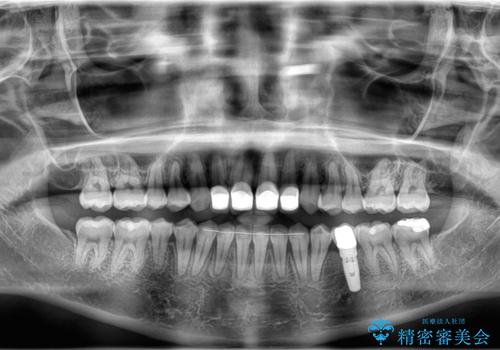

下顎前歯は空隙歯列弓であったので、アンカースクリューとワイヤー装置を用いてスペースを閉じていくこととし、上顎前歯は矯正治療用の仮歯に置き換えた上で、仮歯の大きさを削って小さくしながら、上下前歯部の部分矯正を行うこととしました。

矯正治療後は、仮歯とした上顎前歯をオールセラミッククラウンにて補綴治療を行うこととしました。

日本と海外を拠点に仕事をされていらっしゃるため、数ヶ月治療があいてしまうことがあり、期間はかかりましたが、2年間で望み通りの前歯に仕上げることができました。